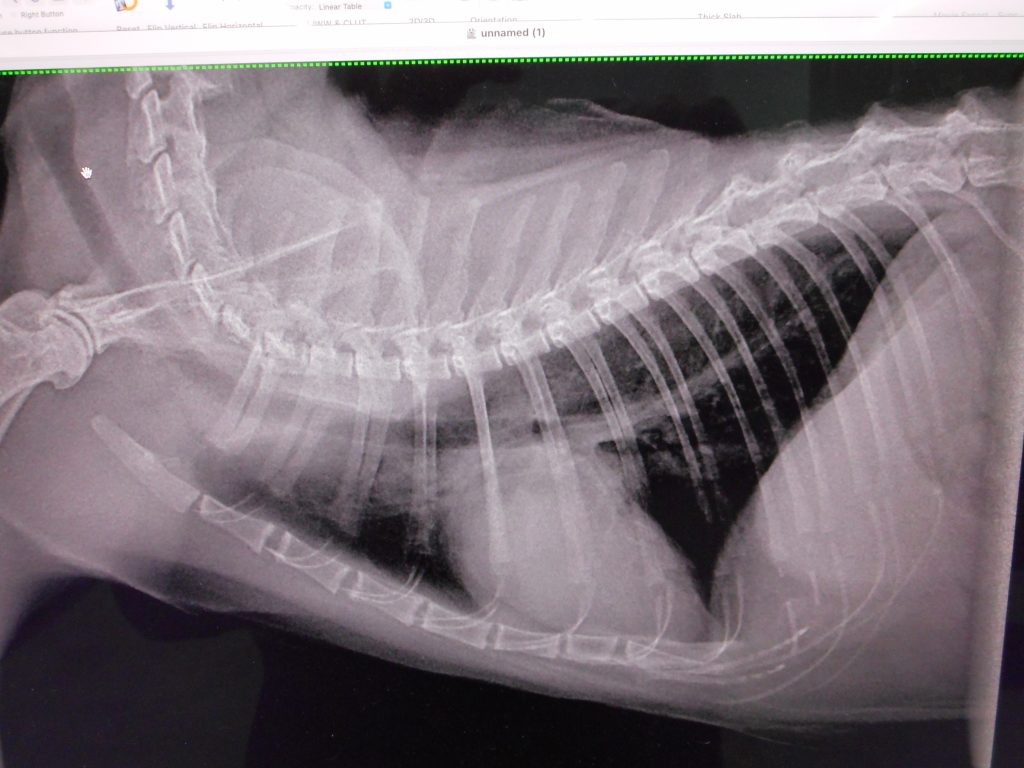

本来は、こんなレントゲン

黒い逆三角形(肺)の中の白い卵型(心臓)がはっきり見えますね

これが正常